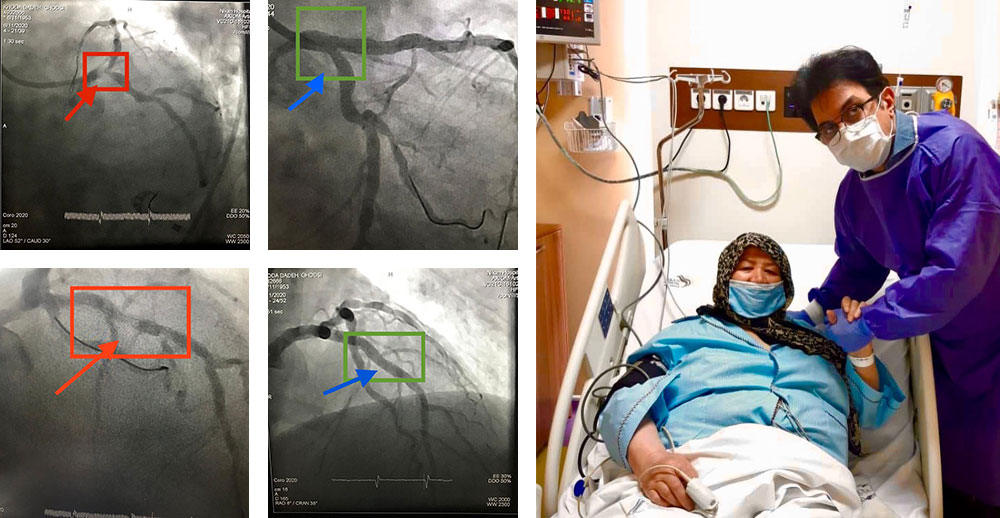

آنژیوپلاستی عروق قلب از طریق دست

آنژیوپلاستی عروق قلب از طریق دست، با رفع عوارض آنژیو از طریق شریان ران، و بدون نیاز به استراحت و بیحرکتی مطلق چند ساعته ی پس از آنژیو

بازکردن رگ اصلی و فرعی بطور همزمان با دو استنت

بیمار عزیز ما با سکته ی قلبی، روز بعد از آنژیوپلاستی با عروق باز شده آماده ی ترخیص است.